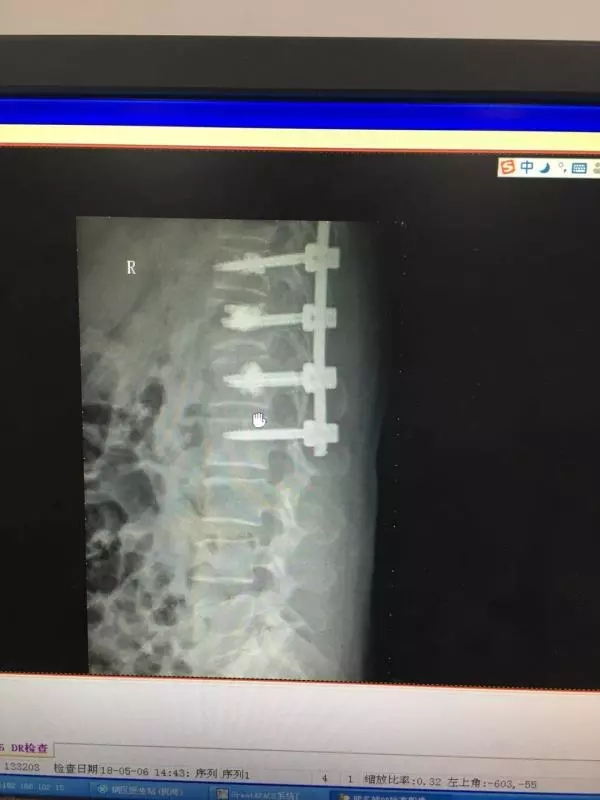

经皮椎弓根螺钉同样也是通过经皮做一小切口,利用C臂机作为医生的眼睛,依次进入导针,扩孔,后期进入椎弓根螺钉。操作稍有不慎,螺钉就可能进入椎管内,造成截瘫。如下图所示: